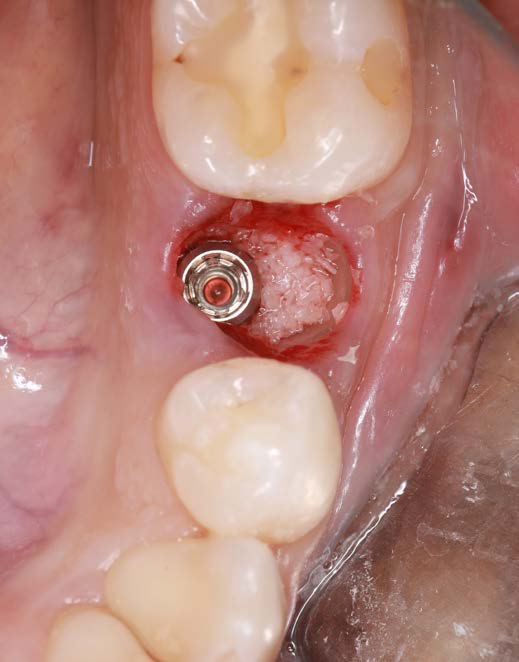

Figure 5: Condition after bone augmentation.

After osteotomy, I placed a 3.75 mm diameter implant, filled the gap between implant and root surface with allogenic bone substitute, inserted a provisional, and later restored with an aesthetic ceramic crown.